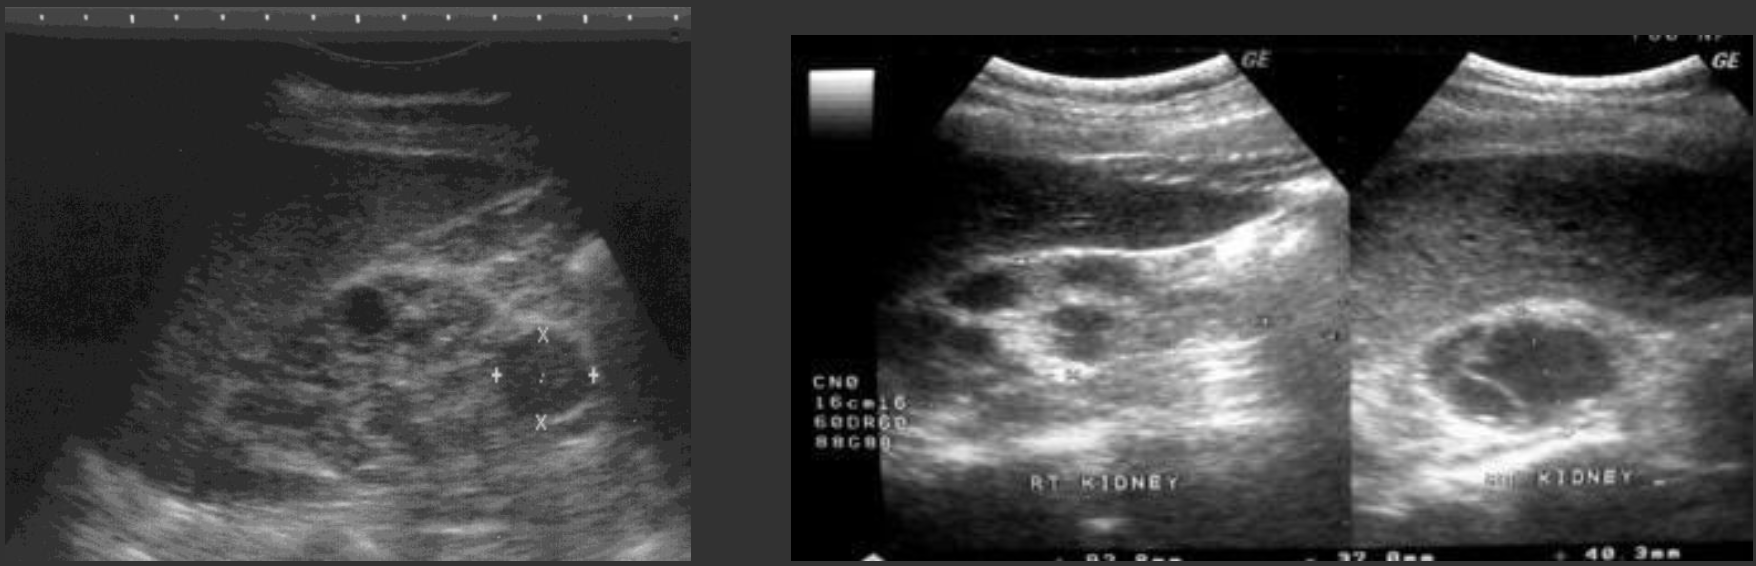

ADPKD (Autosomal Dominant Polycystic Kidney Disease ) → most common hereditary kidney disorder

clinical hx: 30 y/o develops, associated with polycystic liver disease

s/sx: HTN, palpable masses, swollen abdomen, pain w/ rupture, bouts with kidney stones

2D US: bilateral cortical/medullary cysts, varying sizes, simple/hemorrhagic, enlarged bilateral kidneys, normal tissue replaced with cysts,

color doppler: focal echogenic vascular lesion in background of PKD

DDX: parapelvic cysts, hydronephrosis

ARPKD (Autosomal Recessive Polycystic Kidney Disease) → dilated renal collecting tubes

clinical hx: presents in newborns

s/sx: failure to thrive (newbors)

2D US: bilateral enlarged kidneys, echogenic, small cystic changes (1-2 mm)

color doppler: loss of cortical medullary interface

DDX: MCDK